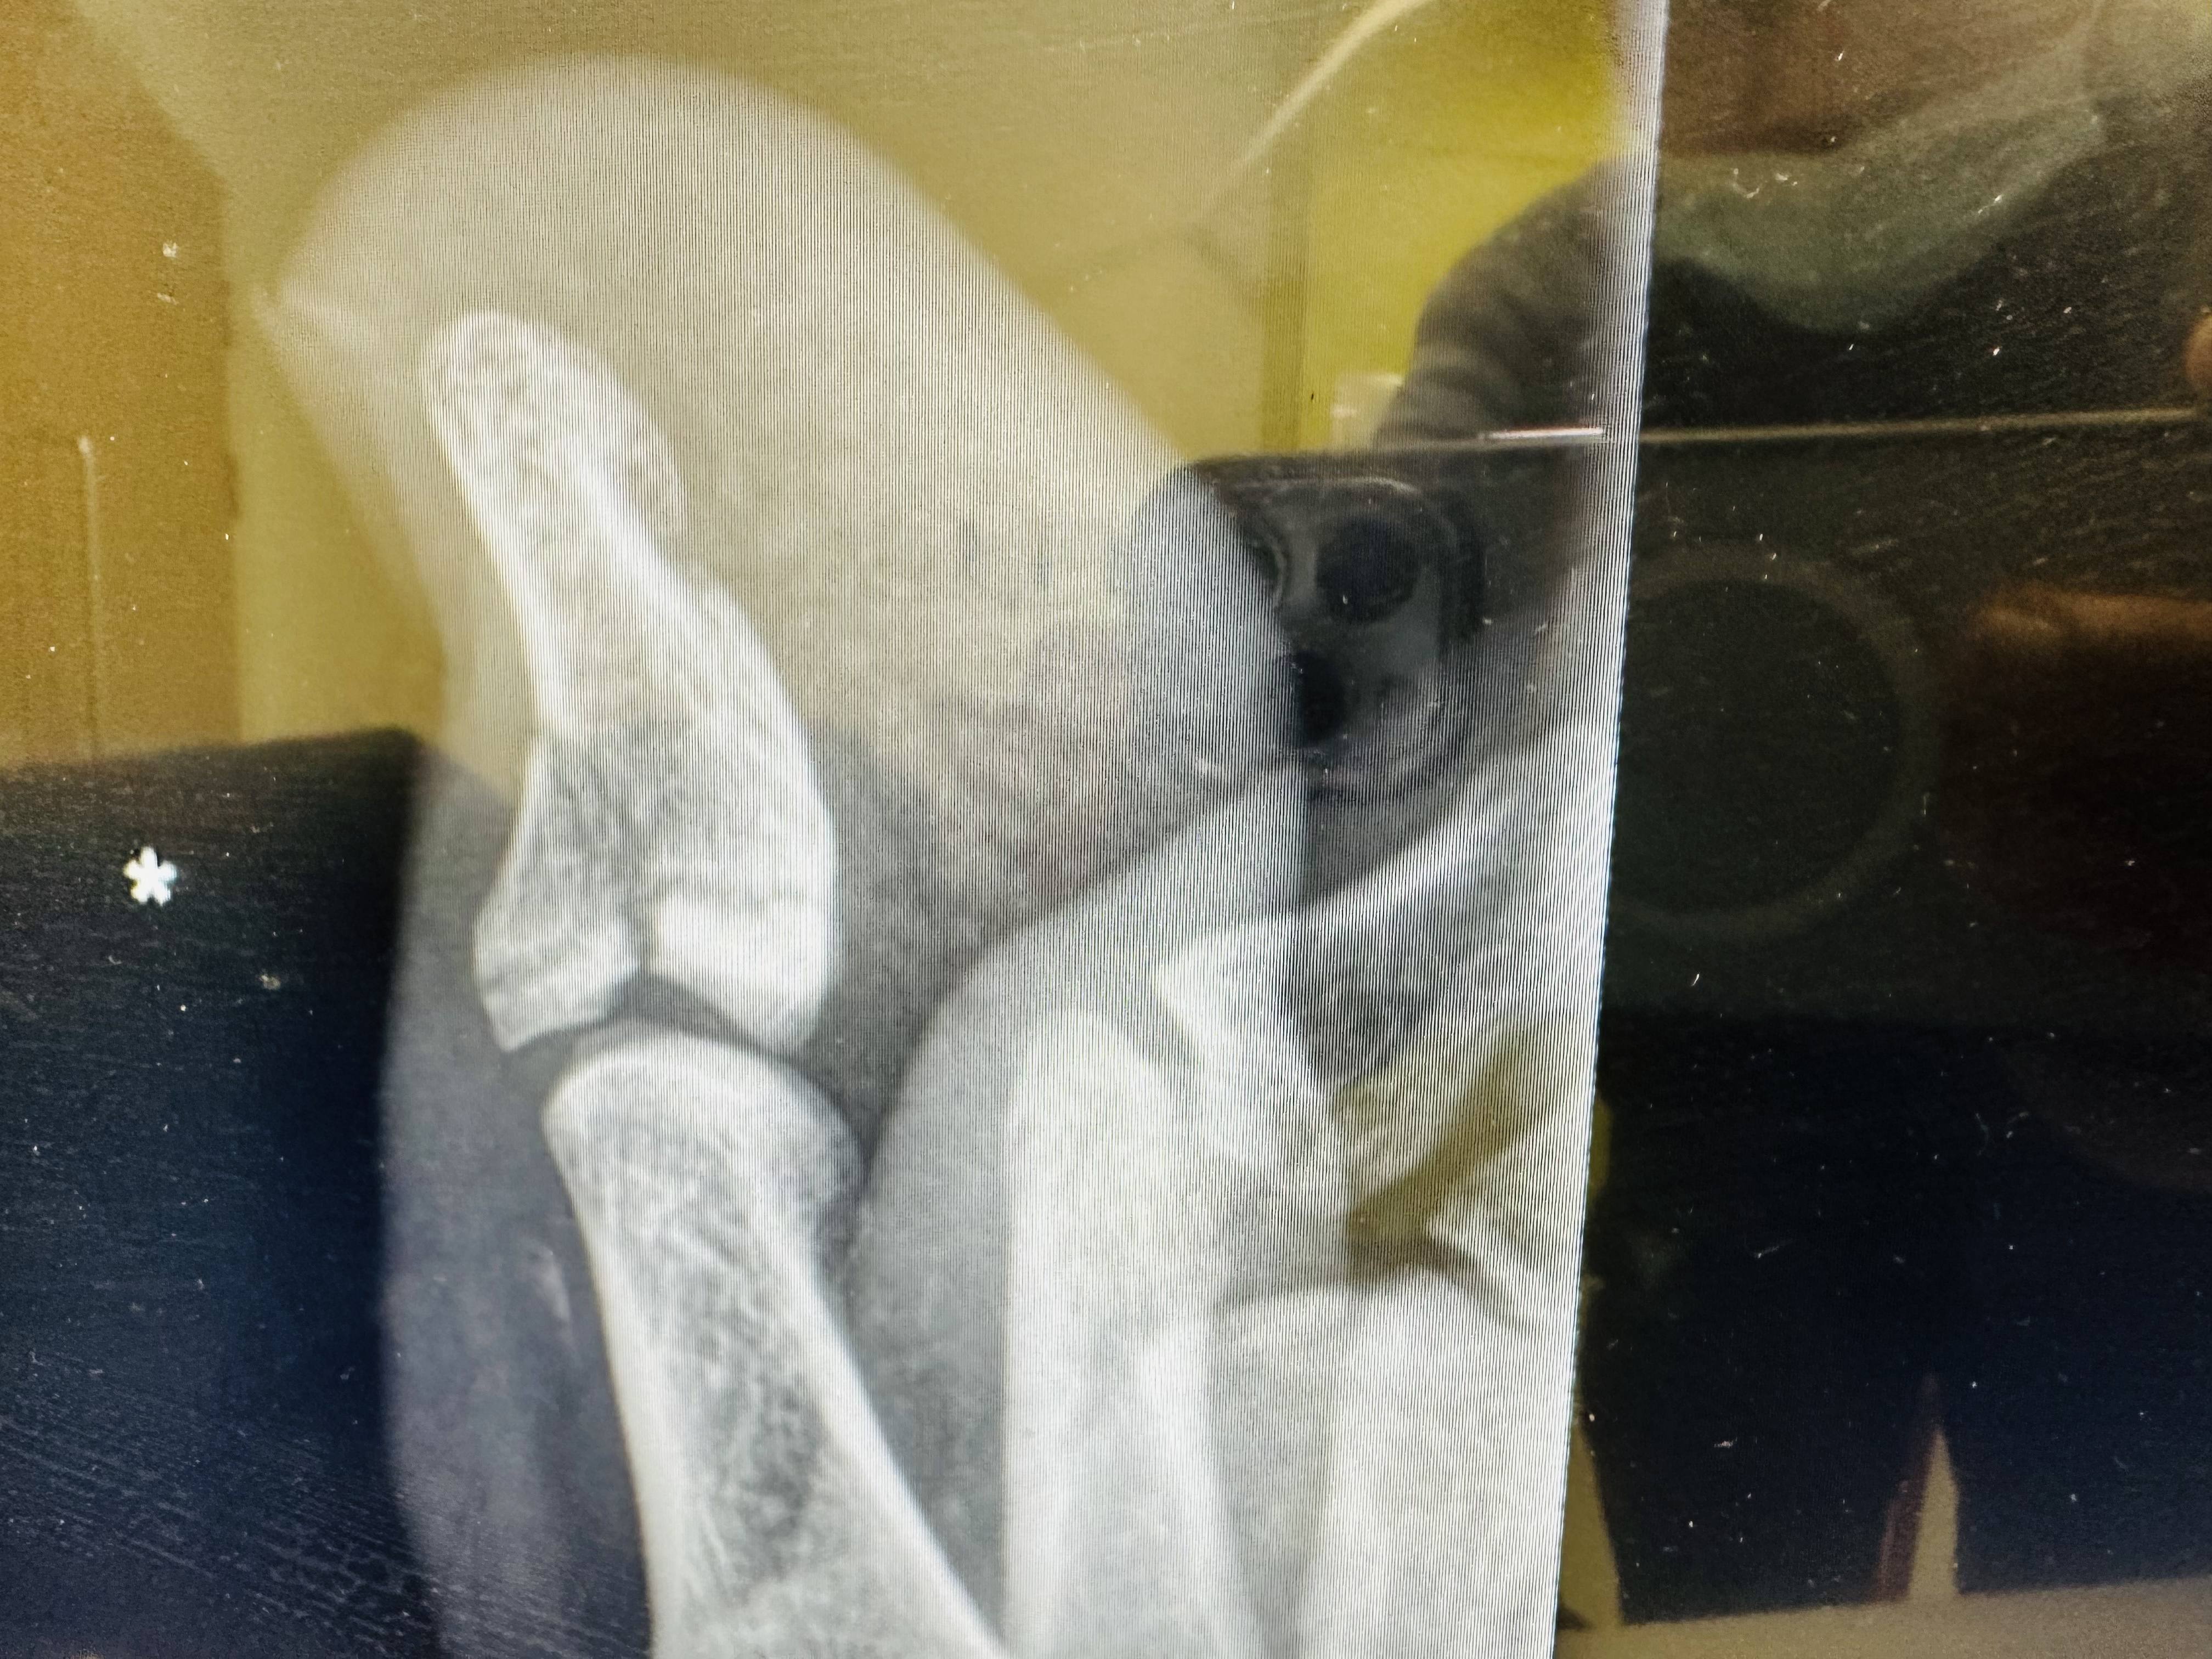

बर्साइटिस का निदान: बर्साइटिस का निदान करने के लिए, आपका आर्थोपेडिक डॉक्टर एक शारीरिक परीक्षा करेगा और आपसे आपके लक्षणों और चिकित्सा के इतिहास के बारे में पूछेगा। वे अन्य स्थितियों से इंकार करने और सूजन की सीमा का आकलन करने के लिए एक्स-रे, एमआरआई, या अल्ट्रासाउंड जैसे इमेजिंग परीक्षणों का भी आदेश दे सकते हैं। आपका डॉक्टर एक संयुक्त आकांक्षा भी कर सकता है, जिसमें सूजन वाले बर्सा से थोड़ी मात्रा में तरल पदार्थ निकाला जाता है और संक्रमण या अन्य अंतर्निहित चिकित्सा स्थितियों के लिए परीक्षण किया जाता है।